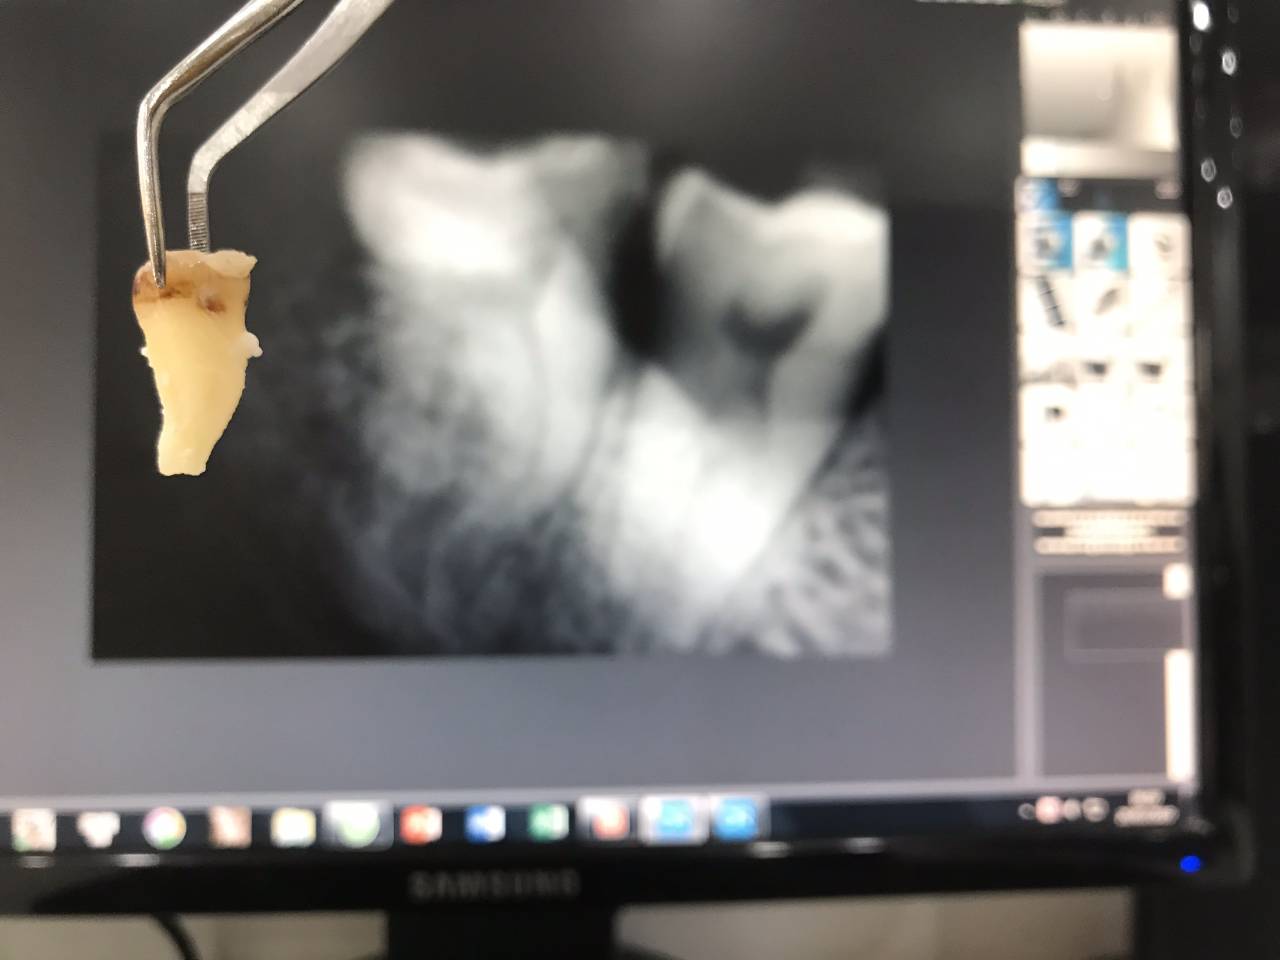

Những điều bạn cần biết khi nhổ răng khôn

Tựu chung lại, cảm giác đau nhức hay sưng tấy, sốt cao khi xuất hiện răng khôn thực sự khiến cho mọi người cảm thấy khó chịu thậm chí ảnh hưởng đến cuộc sống sinh hoạt hằng ngày. Bạn hãy đến tham khảo ý kiến từ nha sĩ để tìm và xác định được phương pháp thích hợp trong trường hợp của bản thân, tránh để sức khỏe bị ảnh hưởng nhé! Nha Khoa Lavita rất hân hành được đồng hành cùng bạn trong quá trình chăm sóc sức khỏe!